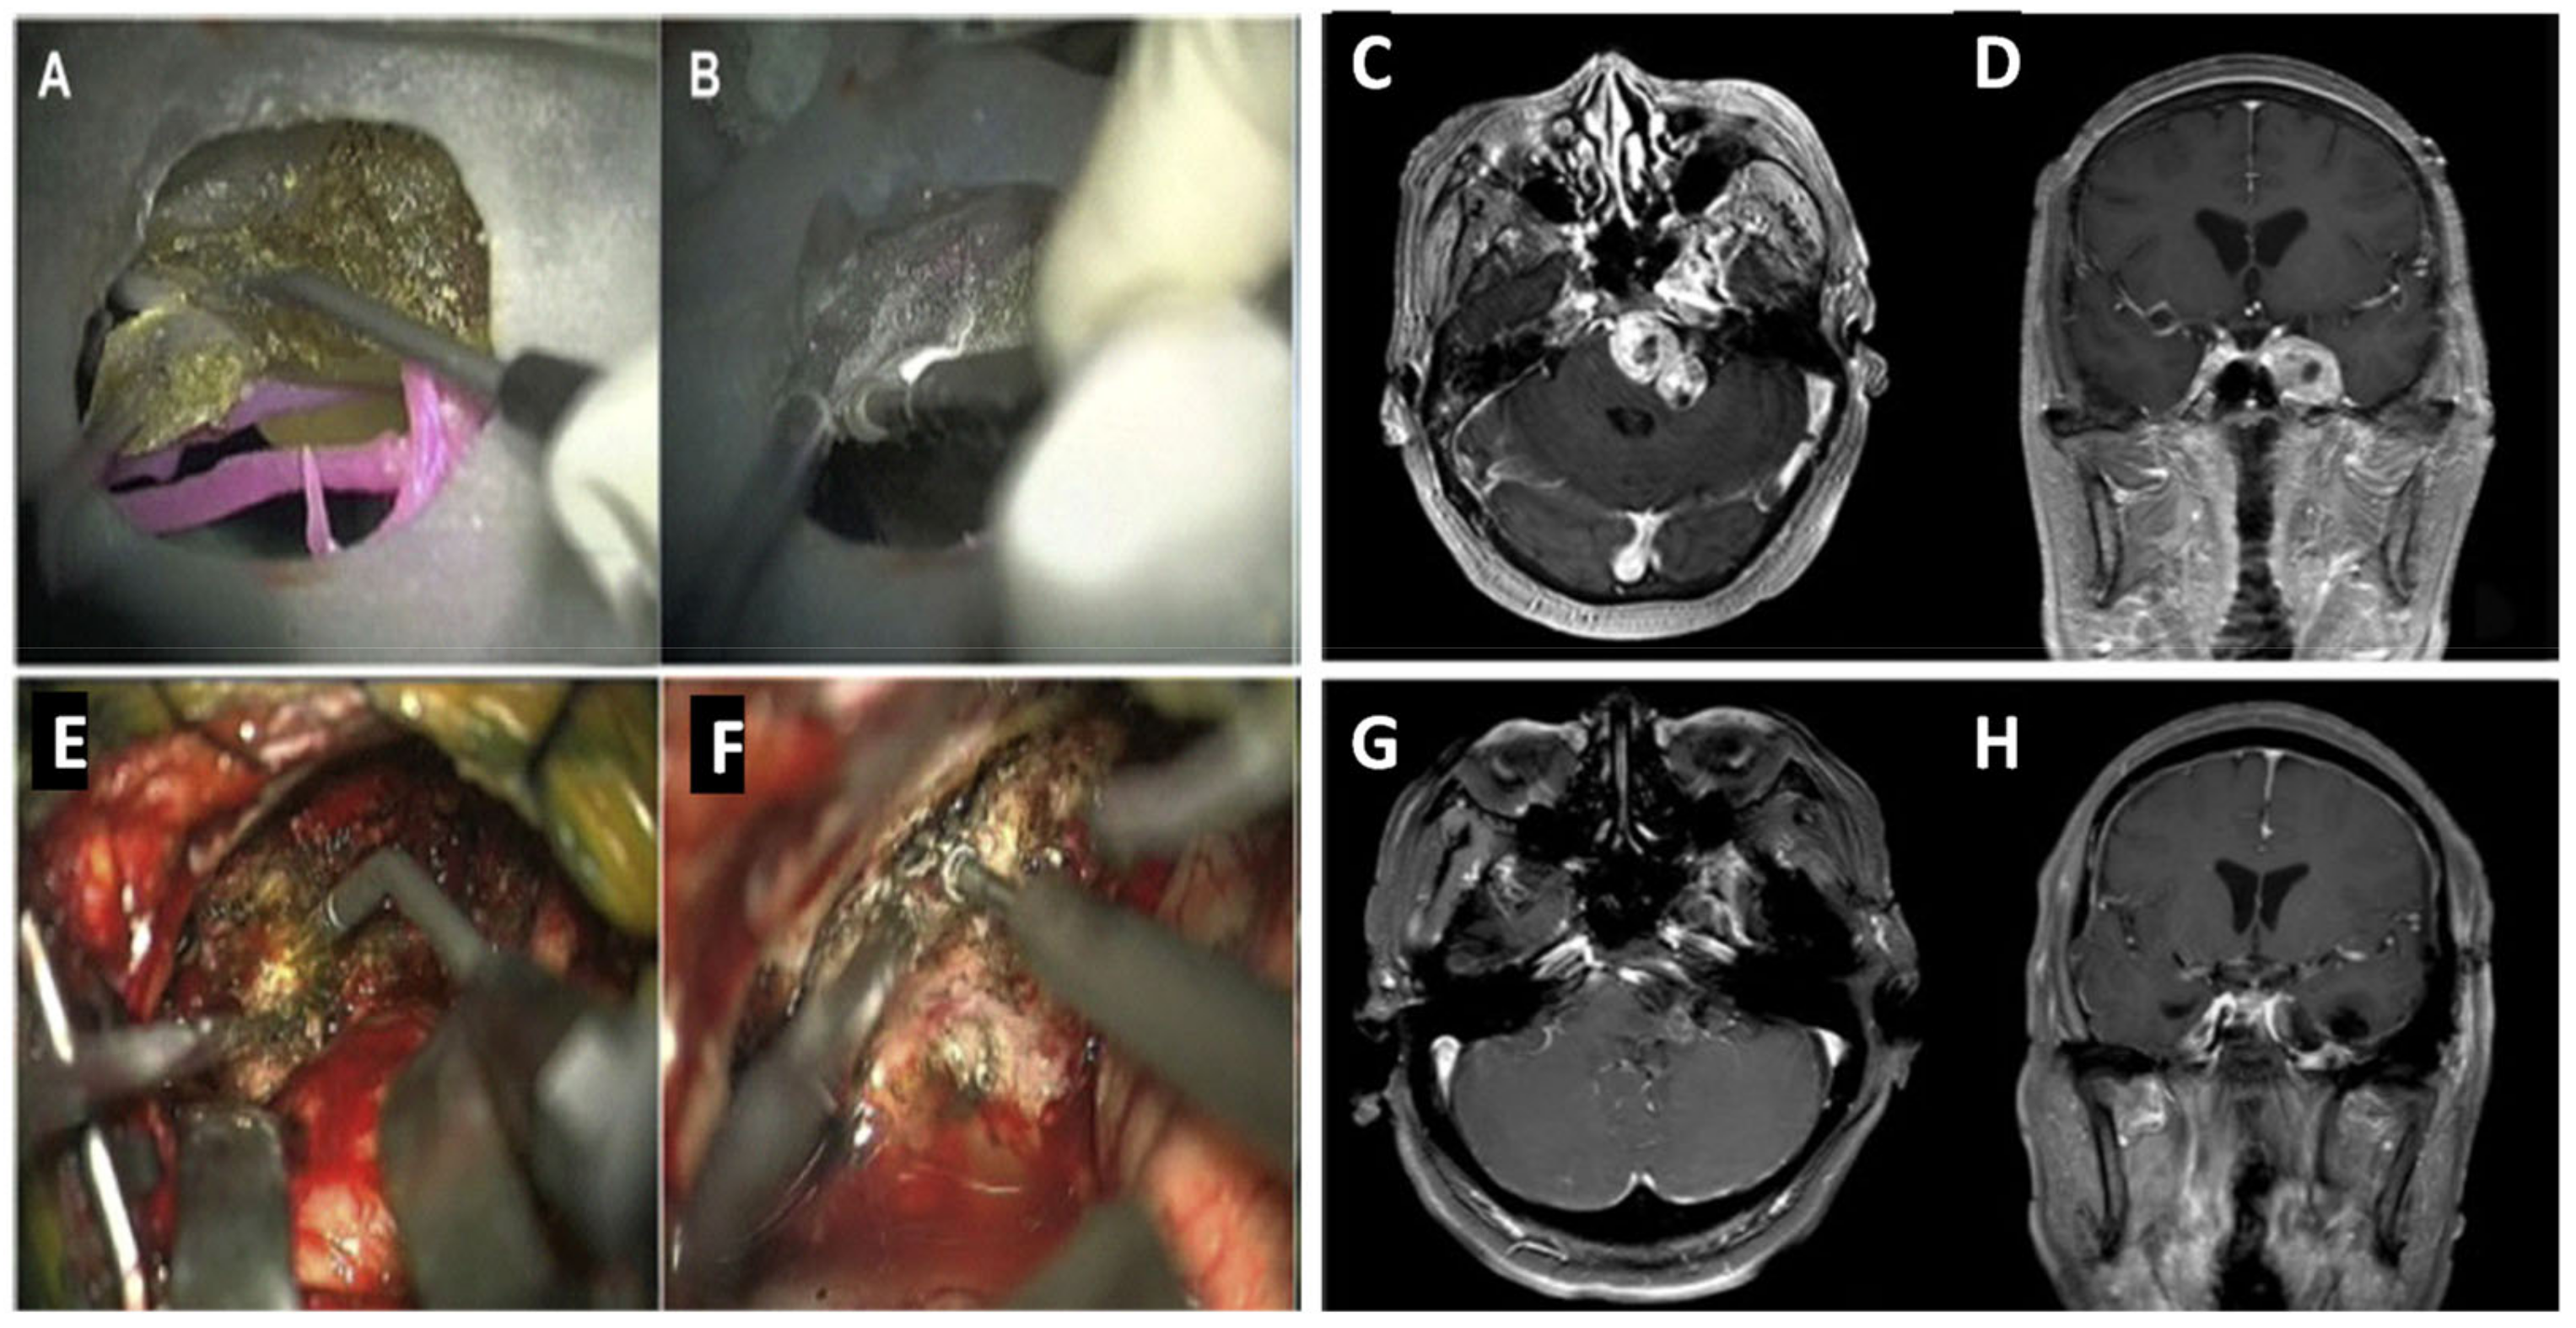

A more recent study constructed models with skull base, cerebral arteries, and brain tumors or aneurysms for simulated surgery [24]. Similarly, the authors of the study used real patient data from computed tomography (CT) scans, MRI, and CTA to obtain imaging data about the aneurysm or tumor. A tectal longitudinal column (TLC) allowed digital information to be collected about the craniocerebral structure. In contrast to previous methods, the PolyJet printing method was used to print the models. Different photosensitive polymers were used, allowing for individual textures and colors, solid skulls, and flexible blood vessels. The first 3D-printed model for brain tumor dissection was conducted. After simulated surgery on the model of patient 1, all tumors appeared to be removed when viewed through a microscope at the middle cranial fossa and posterior fossa (Figure 1A). However, when the model was rotated, the residual tumor could be seen beneath the petrous bone (Figure 1B).

Figure 1.

Simulated surgery and intraoperative scenario. (A)Three-dimensional tumor model resection using left subtemporal keyhole approach and laser-knife. (B) Surgical simulation of removing the residual tumor on the 3D model from the petrous apex after rotation. (C) MRI scan at transverse position displaying tumor growth through middle-posterior cranial fossa preoperation. (D) Tumor observed in the coronal position, preoperation. (E) Real-patient tumor removal with laser-knife. (F) Intraoperation grinding of the petrous apexin. (G) Postoperation MRI scan showing no residual tumor after surgery in transverse view. (H) Coronal position confirming no tumor remaining post operation [24].

The model of patient 2 allowed surgeons to practice separating adhesions between the tumor and blood vessels as it had high spatial correspondence. However, limitations included the texture of the tumor and protection of intracranial nerves as well as hemodynamics. As 3D technology advances, different techniques and materials may allow for the addition of these. After simulated surgeries with models, real-life surgery took place, allowing surgeons to put their knowledge into practice. Figure 1G,H are MRI images confirming that no residual tumor remained in the patient after real-life surgery. Although images from simulated surgery (Figure 1A,B) are not identical to the real-life surgery (Figure 1E,F), it did not prevent refining the strategic planning for surgery. Overall, this study indicated that the experience gained from the simulated surgery prevented unnecessary exploration, producing a minimally invasive, faster, and more effective surgery, ultimately improving the outcome for patients [25].